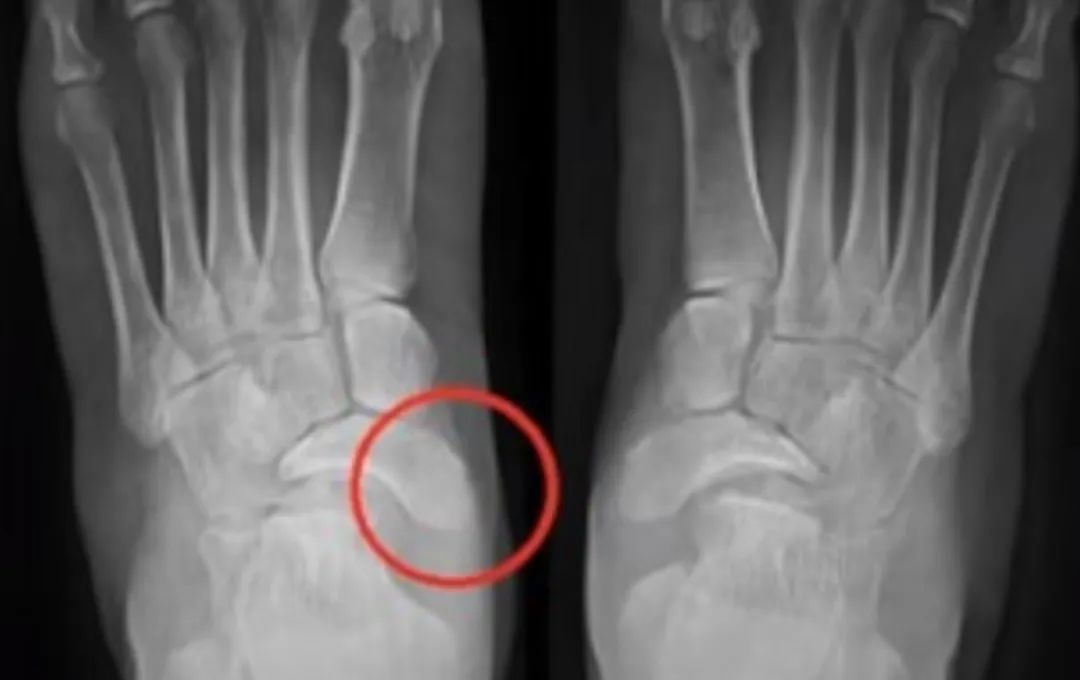

上图为纳达尔双脚医学影像图

在医学上,纳达尔的左脚伤病被称为穆勒·魏斯综合症(Muller Weiss syndrome,中国称之为足舟状骨坏死)。我们脚的骨头关节构造非常复杂,26块骨头通过33个关节相互连接,这为20块肌肉提供了稳固的支撑。你可以把我们脚的整体结构想象成一个拱形的高架桥。

患有魏斯综合症的患者,其足部中央的舟状骨先天发育不良或后天受外力导致萎缩或受损,于是就造成足弓变形,患者走路时就会感到疼痛。如果只是轻微受损,一般不太影响日常生活,如果受损达到一定程度或是运动过度,则会有明显的疼痛感。

纳达尔左脚的舟状骨在童年之后没有完全骨化,导致其难以承受大强度运动带来的压力。通常来说,选用一个更合适的鞋垫可以让足弓得到支撑,疼痛症状可以得到缓解。